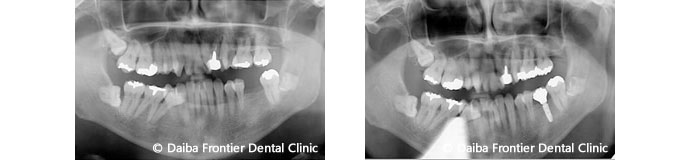

上記左はインプラント術前、右はインプラント術後の画像です。術後は半年に1度のメンテナンス・クリーニングが大切です。他の歯のメンテナンスももちろんお勧めします。患者様に長く使って欲しい気持ちでこだわってインプラント治療を行っているので、メンテナンスを忘れないで大切に使って欲しいと思います。